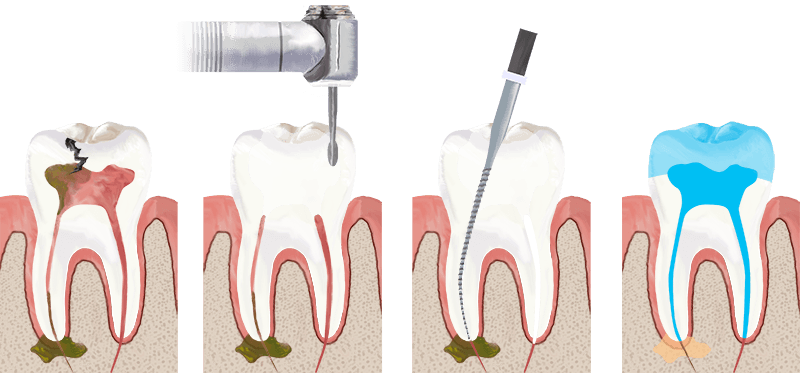

Tratamentul endodontic este procedura prin care se îndepărtează țesutul pulpar inflamat sau infectat din interiorul dintelui, canalele sunt dezinfectate și apoi sigilate ermetic. Scopul este salvarea dintelui și prevenirea infecțiilor viitoare.

B. Cum se realizează tratamentul endodontic? Etapele esențiale

4. Accesul endodontic și îndepărtarea pulpei

Se îndepărtează țesutul inflamat/infectat.

5. Instrumentarea canalelor

Cu ace manuale sau rotative din NiTi (nichel-titan), care oferă:

7. Obturarea canalelor

Se folosește gutapercă și un ciment endodontic bioceramic sau pe bază de rășini. Scopul este sigilarea completă.

8. Reconstrucția dintelui

Poate necesita:

- obturație directă

- pivot din fibră de sticlă dacă dintele este slăbit

- coroană dentară pentru dinți posteriori sau afectați sever